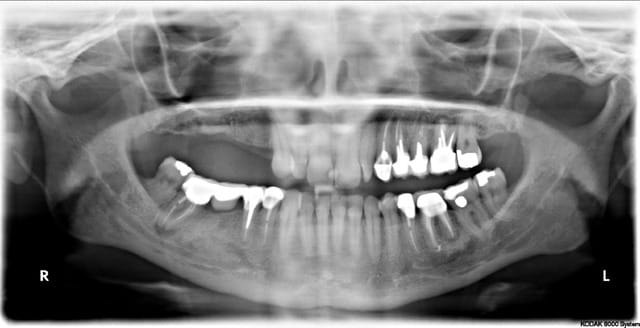

oui ça fait un gros prélèvement, c'est pour un cas particulier ou je dois virer 24, 25 et 26 avec de grosses lésions apicales et latérales, ou je voudrais conserver le maximum de volume osseux pour pouvoir implanter dans de bonnes conditions.

ci joint la pano et les coupes scan.